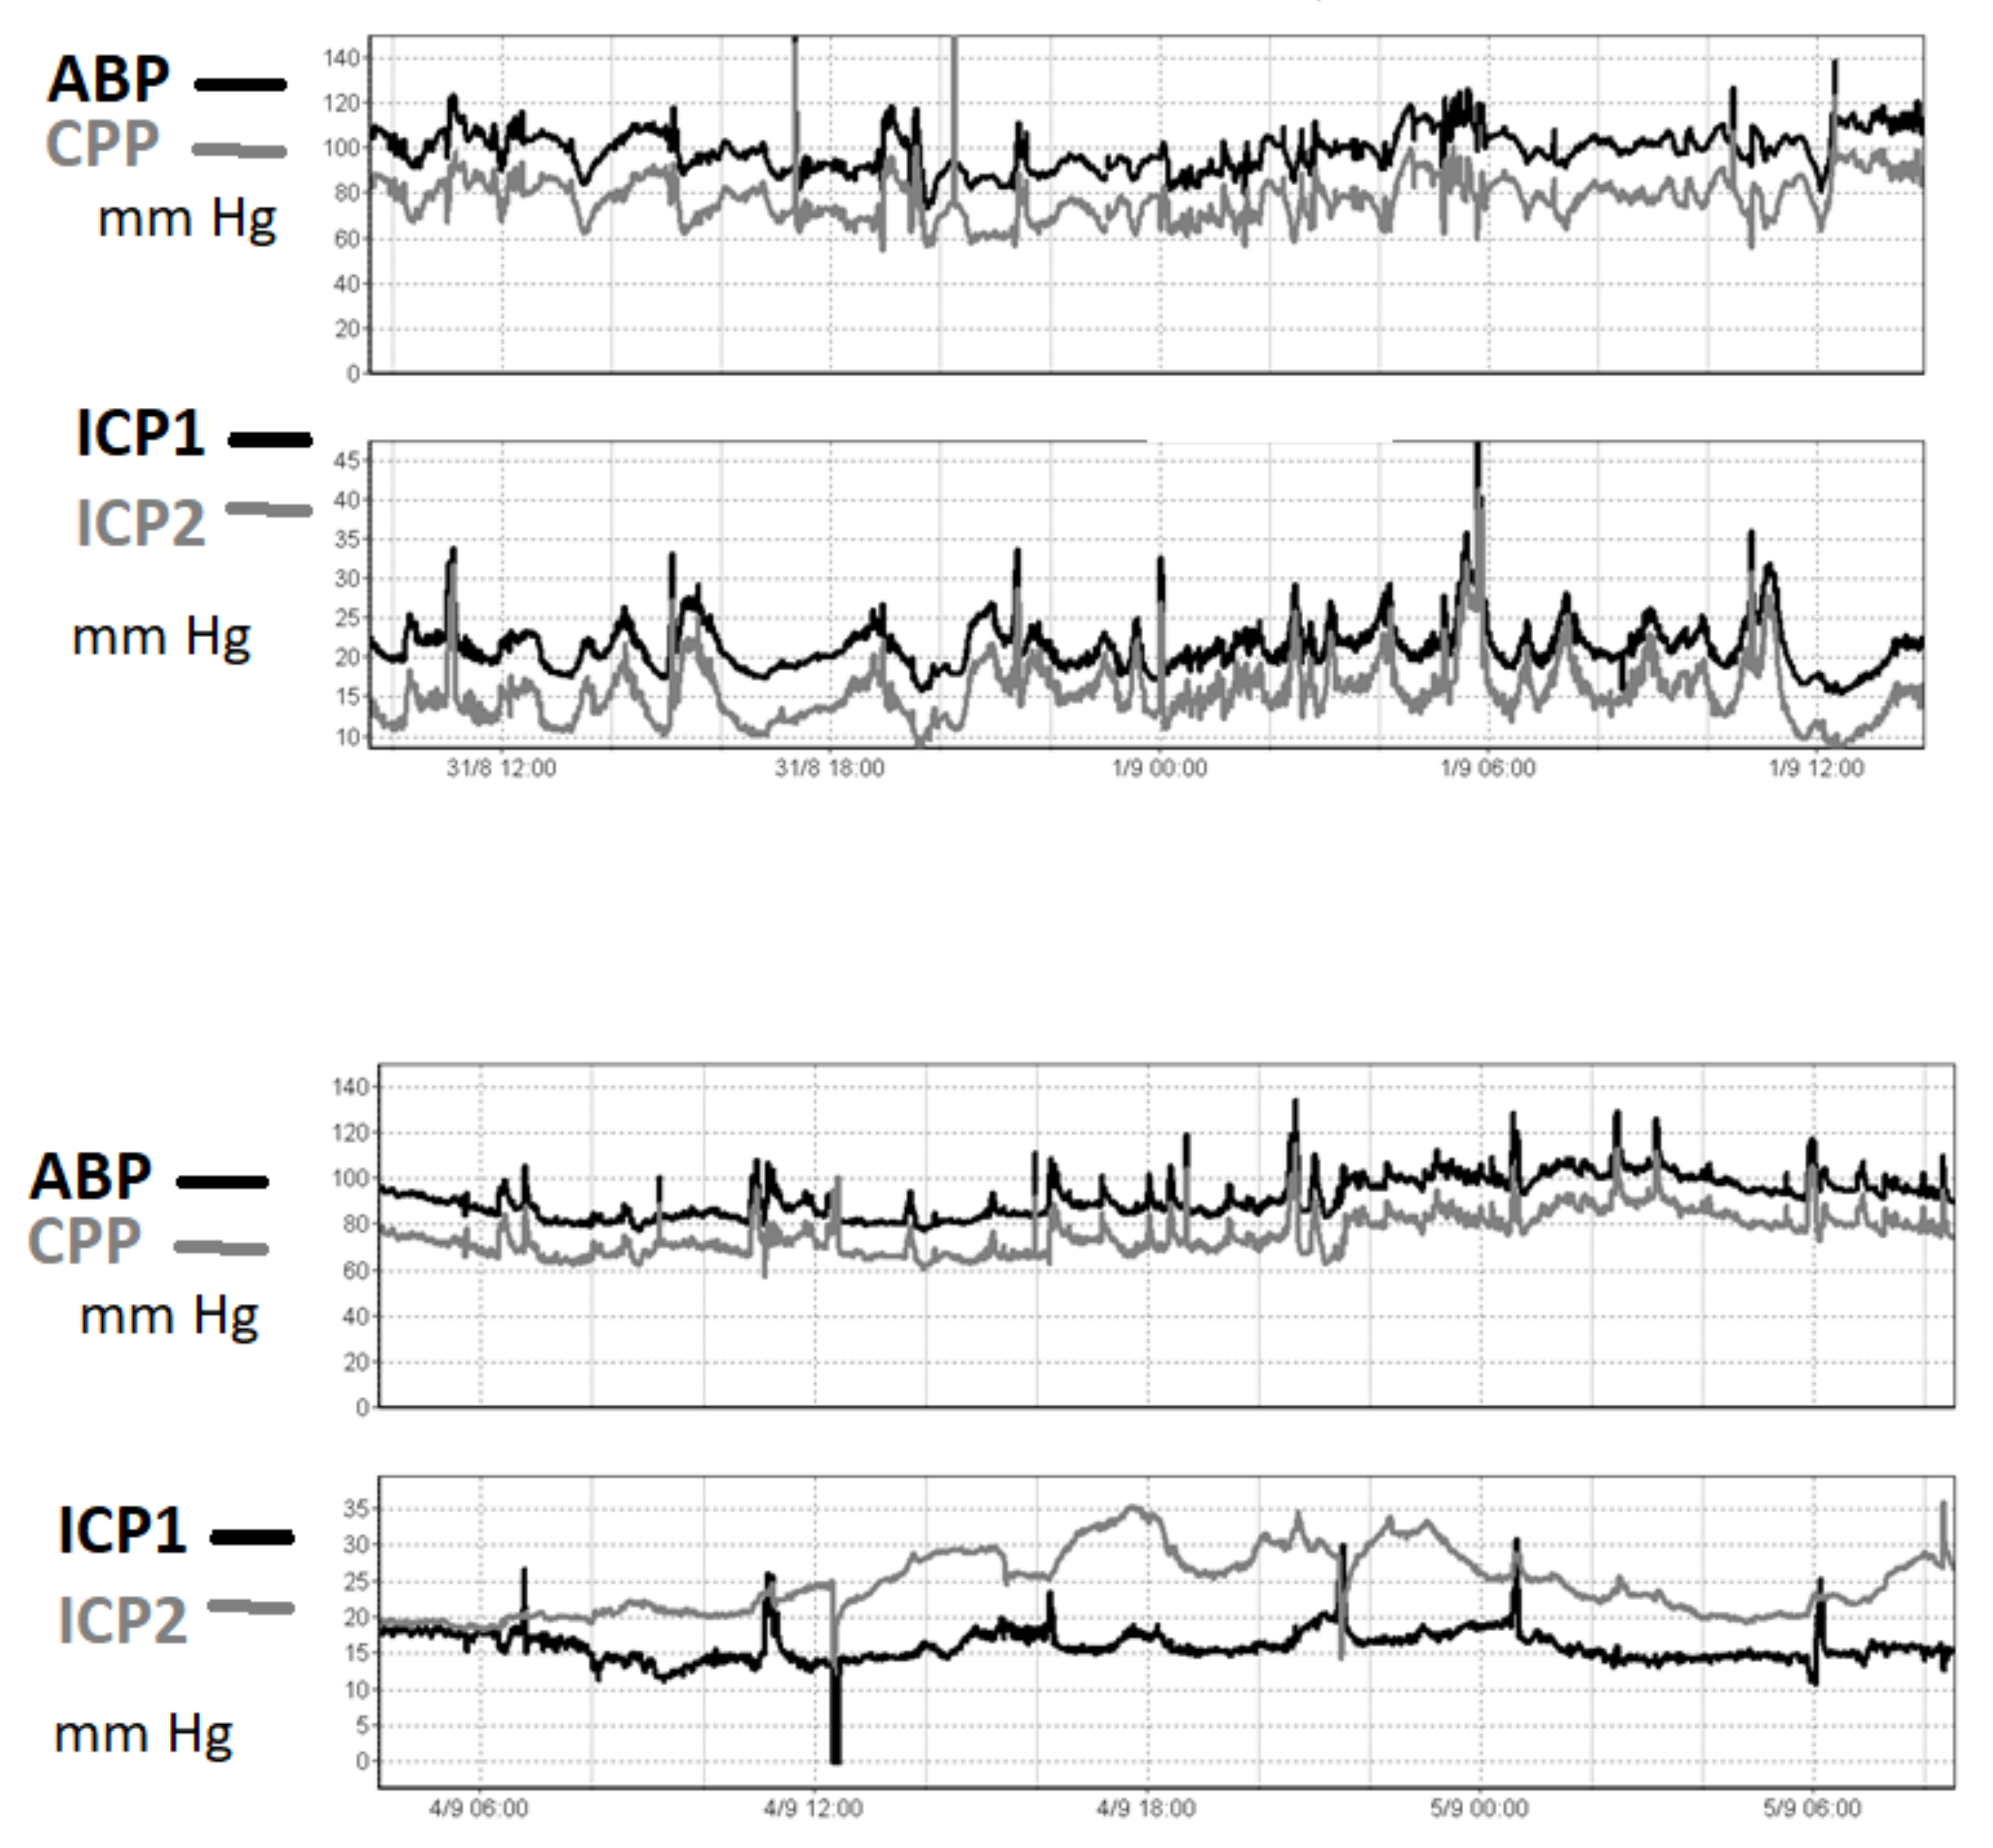

Even though the correlation between two microsensors reporting simultaneously may vary over time and in terms of absolute value (Figure 2), intraparenchymal ICP measurements should be reliable.

Figure 2.

An ICP recording in one patient after TBI. ICP was recorded using two intraparenchymal microsensors (ICP- left hemisphere, ICP2- right hemisphere). In the upper panel, the two pressures are very well correlated in time, even though around 6 mm Hg of constant difference between the two readings is observed. In the lower panel, in contrast, the difference is seen to have increased to 20 mm Hg three days later. This patient suffered from diffuse brain injury without midline shift. The reason for the difference in readings was unknown. The true value of the ICP cannot be determined from these sensors.